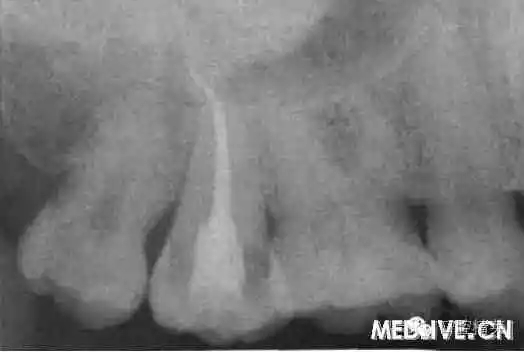

7⊥頜面中央窩見開髓洞型,叩痛(++),無松動(dòng)。X線片示7⊥牙根融合為一彎曲單根,根管粗大,根尖1/3偏向遠(yuǎn)中,無充填物,未見髓室底(圖1上)。錐形束C’r檢查示:根管橫斷面僅見一個(gè)根管口略呈啞鈴形,頰舌向管徑粗大,中下1,3存在牙本質(zhì)島,根尖1,3明顯彎曲偏向遠(yuǎn)中,彎曲角度為34.30(圖2上)。

圖1上:初診;下:根管充填后